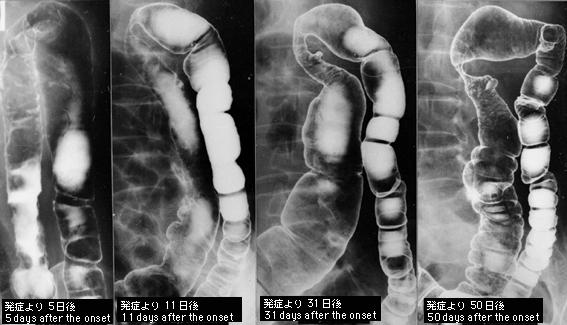

50日内X光片4次观察到其推移的狭窄型缺血性大肠炎

炎症性・溃疡性疾患/缺血性大肠炎

部位(按器官分)

检查方法